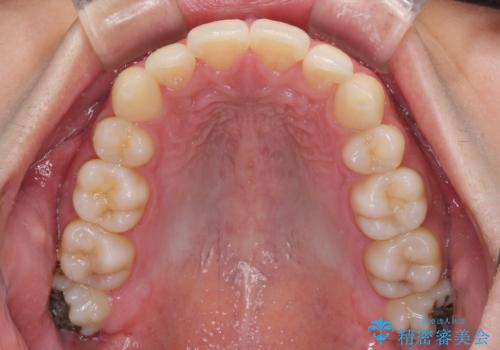

矯正治療の後戻りをインビザライン・ライトで解消

- 矯正治療の後戻りを気にして来院された患者様です。

後戻りは軽微であったので、インビザライン・ライトにより矯正治療を行うこととしました。

インビザライン・ライトは提供されるマウスピースの数に制限があり、通常のタイプよりもマウスピース提供期間が短くなっている一方、安価に治療を行うことができるプランです。

治療のゴールも変更できないため、軽微な歯列不正や、後戻り改善などに適しています。

矯正治療後は、再度後戻りすることを極力回避するために、下顎前歯の舌側を細いワイヤーを用いて保定することとしました。